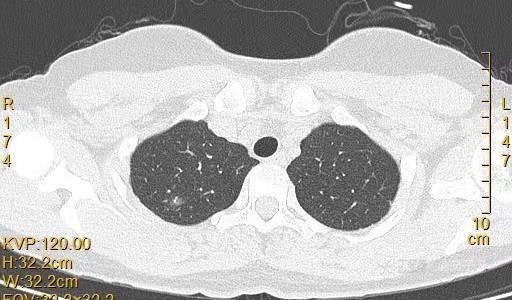

患者女,44岁,无特殊症状,做体检时发现右肺结节。查到1年前的体检CT片,右上肺当时就有一个直径约3mm的微小结节。两次检查检查图片如下:

以下三张为1年前CT片: